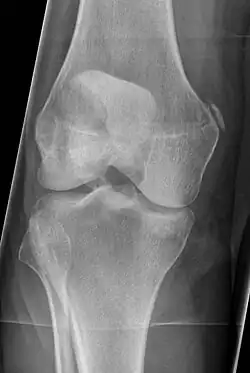

Diagnosis is typically made on radiographs demonstrating the Pellegrini-Stieda syndrome sign accompanied by pain or restriction of range-of-motion of the knee joint.[2] Pellegrini-Stieda syndrome sign is typically described by a longitudinally linear opacity, which is a process that is describes characteristic of calcification in the soft tissue located medial to the medial femoral condyle.[2] This calcification seen on imaging represents the ossification of the medial collateral ligament, which typically does not develop until approximately three weeks after the initial injury.[2]It is important to note to distinguish this radiographic finding from that of a medial femoral condyle avulsion fracture, which is an injury in which a pulling force of a tendon or ligament fractures away a piece of the bone from its attachment site.[2]

Alternative classification syndrome for Pellegrini-Stieda lesions of Type 1 through Type 4 based on their location:[2]

- Type 1- is referred to as a beak-like appearance and describes the ossification arising from the femur and extending inferiorly in the medial collateral ligament.

- Type 2-is defines a tear-drop pattern, localized within the medial collateral ligament without any attachment to the femur.

- Type 3-presents as an elongated ossification superior to the femur lying in the distal adductor magnus tendon.

- Type 4-is also characterized as a beak-like appearance arising from the femur. However, there are some cases where this ossification extends into both the medial collateral ligament and adductor magnus tendon. In then, the original attribution of the syndrome to the medial collateral ligament may now be outdated as many publications have suggested concomitant and even sometimes preferential involvement of the adductor magnus tendon, medial head of the gastrocnemius, or medial patellofemoral ligament.[2]